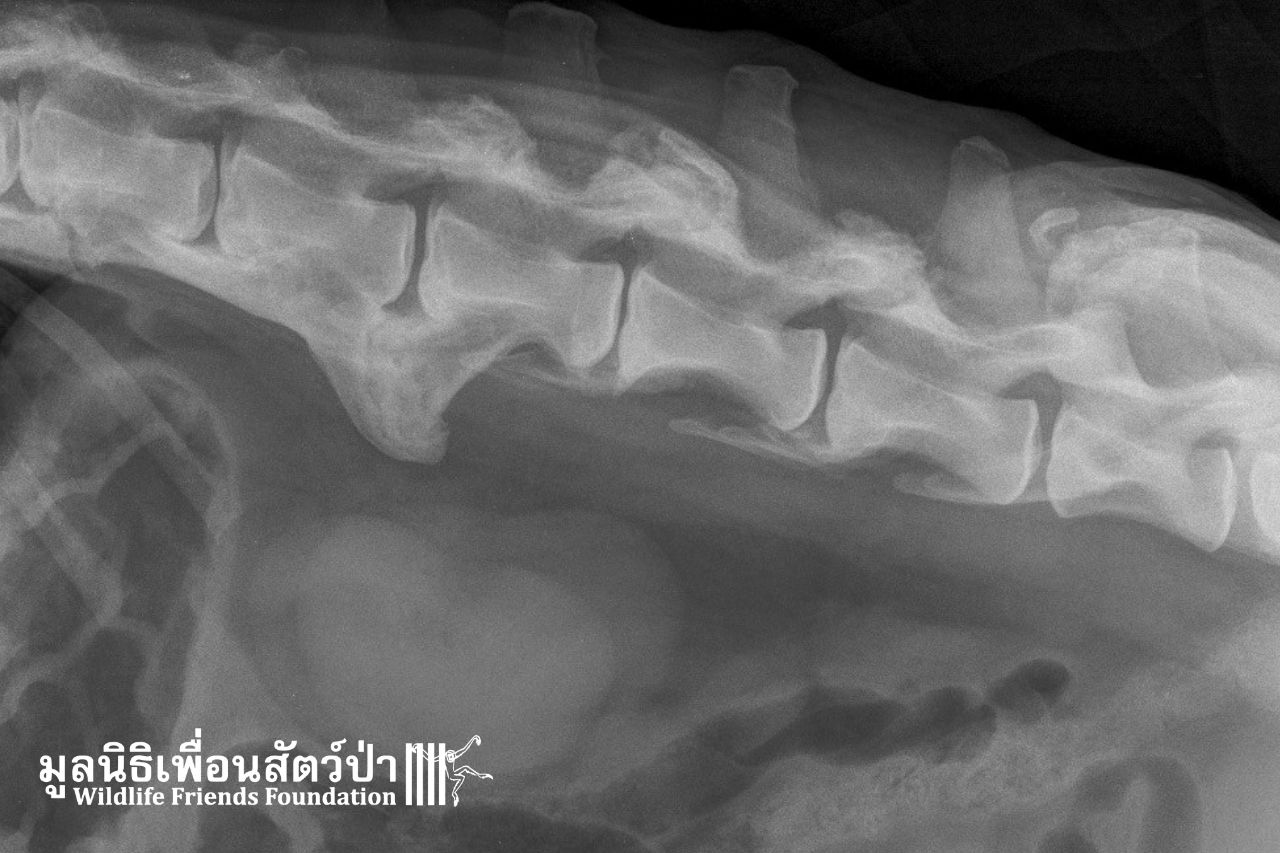

Pin’s health check showed a deformed spine

The x-rays sadly show that Pin’s spine is deformed.

As Pin has got stronger, our vet team recently sedated her to do a thorough health check. The x-rays revealed that she has an overgrown bone in her spine, which explains the way she walks. We are in discussion with specialist vets to formulate a long-term plan for her care.